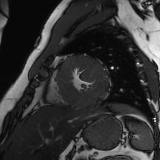

Refer to caption

Figure 2: Examples of tracking results using the proposed method (MPN-C). From left column to right: ED frame, ES frame, warped frame from ED, overlay of ES frame and the warped mask, and estimated motion field using HSV color coding. The color coding wheel legend indicates the motion directions.